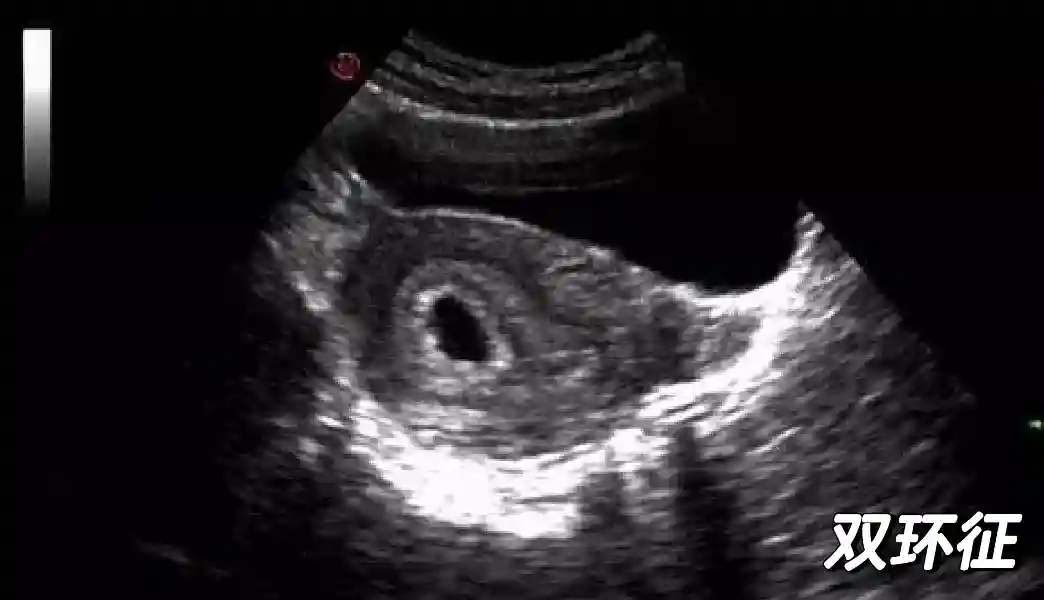

1️⃣妊娠囊:早期妊娠囊:正常妊娠囊位于宫腔上段,表现为宫腔内圆形或椭圆形的无回声区,周边为完整的、厚度均匀的强回声环,强回声环厚度≥2mm,强回声是妊娠绒毛的回声,随着妊娠囊的增大,形成特征性的“双环征” ,10周以后消失。正常的妊娠囊增长速度是平均 1 mm /d。